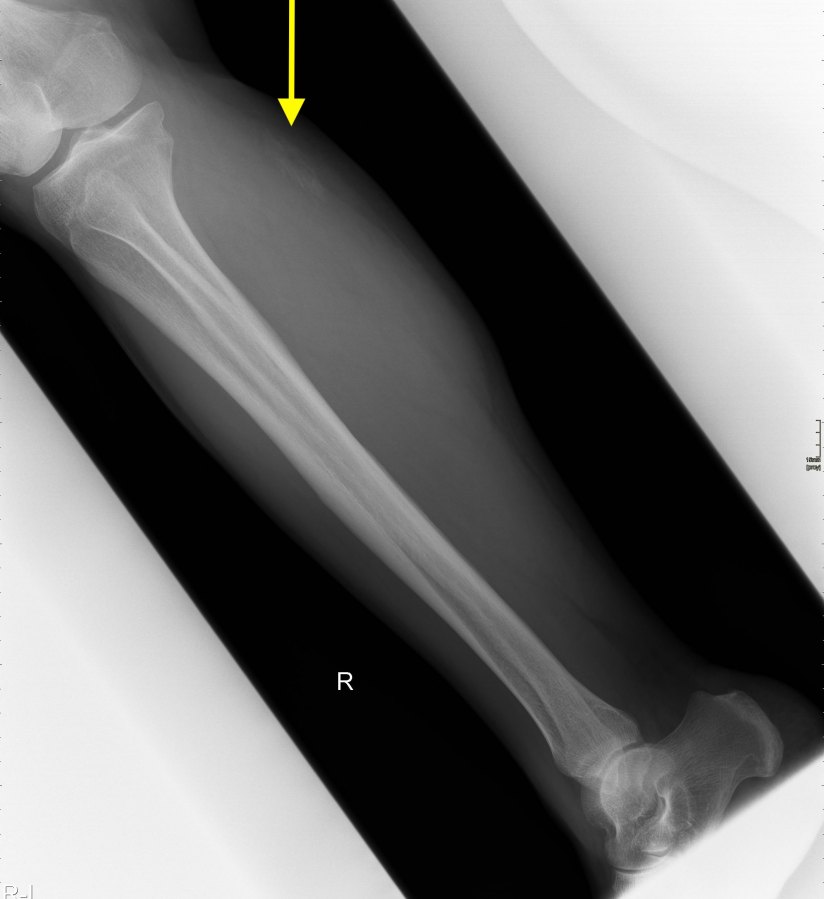

Aumento vasto intermedio

En este caso final una mujer acude a realizarse una ecografía con una petición de su médico de cabecera, viene por aumento del calibre del muslo anterior, no refiere dolor, no cuenta traumatismo previo.

La exploración es la habitual, revisión sistemática de toda la ecoarquitectura musculoesquelética de la cara anterior del muslo, dirigido al Cuádriceps.

Me llama poderosamente la atención, lo recuerdo perfectamente, la normalidad del recto anterior, pero después de buscar un poco observo como el vasto intermedio si está «distinto», algo heterogéneo, voy a comparar con el lado contralateral y bingo¡ el vasto intermedio, que es de esa musculatura «que nunca tiene nada», modo «ironía on», te sorprende…y la ecografía muscular es como el océano, nunca puedes confiarte…

Mira las imágenes y tu misma te darás cuenta:

La zona que presenta mayor abombamiento y empastamiento (cara lateral del muslo izquierdo), se visualiza aumento del grosor del fascículo muscular correspondiente con el vasto intermedio, sin poder evidenciarse la presencia de lesiones definidas. El diagnóstico es un aumento difuso e inespecífico del Vasto Intermedio, sin masas ni roturas. A valorar con RMN.